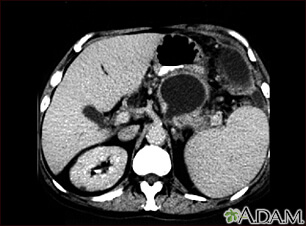

Комп'ютерна томографія (КТ) – це метод медичної візуалізації, який поєднує в собі рентгенівські та комп'ютерні технології для створення детальних зображень внутрішньої частини тіла. Широко використовується для діагностики та моніторингу захворювань органів черевної порожнини завдяки високій роздільній здатності та можливості отримувати зображення в декількох площинах. У цій статті ми розглянемо, як КТ використовується в діагностиці захворювань органів черевної порожнини, її переваги, обмеження та проблеми безпеки.

КТ працює за допомогою рентгенівського випромінювання для отримання численних зображень поперечного перерізу тіла. Рентгенівська трубка і детектори обертаються навколо пацієнта, а отримані дані обробляються комп'ютером для створення детальних зображень органів і структур. КТ може проводитися з контрастними речовинами або без них – речовинами, що вводяться в кров для виділення певних органів і структур.

КТ широко використовується для оцінки захворювань печінки, таких як цироз, жирова дистрофія печінки та пухлини печінки. КТ може виявити утворення в печінці розміром 2-3 мм і може точно диференціювати доброякісні та злоякісні ураження. КТ також може оцінити розміри пухлин печінки та їх зв'язок із сусідніми структурами, що важливо для планування лікування.